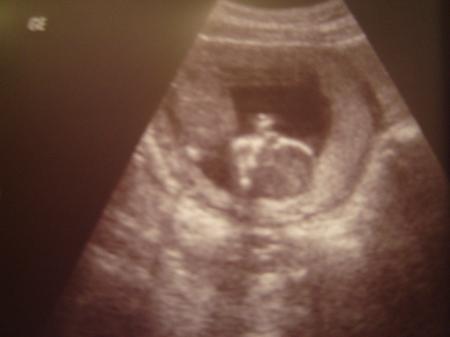

Natürlich nur mit guten Nachrichten! Baby geht es gut und ich wurde auf die 15. Woche vorgesetz und bleibe bei dem ET 05.08.! Es passt nicht mehr auf den US-Schirm, so groß ist es schon. Darf in 2 Wochen wieder kommen. Wir machen das so bis ich es spüre dann setzen wir es auf einen 4 wöchigen Termin. Hier nun noch das Foto von meinem Zwergl!

Bild zu Zurück vom Fa - Forum für August - Mamis

Sie konnte es nicht richtig messen und sagte 6,5 cm. Aber am letzten Donnerstag war ich bei der NFM. Da war das Kleine 6,9cm und entsprach einer 13+0 (also 14. Woche) Ich war aber in der 13. Woche dachte ich, da sie mich einmal eine Woche zurück gesetzt hatte. Na egal, ich bin jetzt wieder richtig. Es war von Anfang an der 05.08. und ich wurde zwischen durch eine Woche zurück gesetzt und jetzt geht´s eine Woche wieder vor. Das Baby kommt eh wenn es will, ob am 05.08 oder 10.08....egal, raus muss es ja doch!